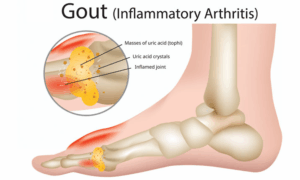

痛風発作の真犯人は尿酸結晶です。繰り返される痛風発作が解消されるためには、尿酸結晶が溶解して除去されなければならず、再発の悪循環を断ち切るためには「尿酸結晶化イベント」を予防しなければなりません。

尿酸値が高くても尿酸結晶が形成されなければ痛風には移行しません。逆に尿酸値が低くても尿酸結晶が形成されれば痛風発作が始まります。時間が経過して発作が治まっても、尿酸結晶に感作された免疫系は炎症状態を維持するため、尿酸が結晶化しようとする兆候が見られると、再び痛風が再発することになります。

高尿酸血症は血中尿酸値が正常より高い状態です。尿酸の正常範囲は女性の場合6mg/dl以下、男性の場合6.5~7.0mg/dl以下とされています。成人男性の場合、体内に約1200mg程度の尿酸が存在し、女性の場合はその半分程度です。尿酸は水溶性ですが、水に溶けない尿酸結晶が体内に沈着している場合、つまり痛風を患っている場合には、尿酸値が体内の実際の状態を反映できないことがあります。